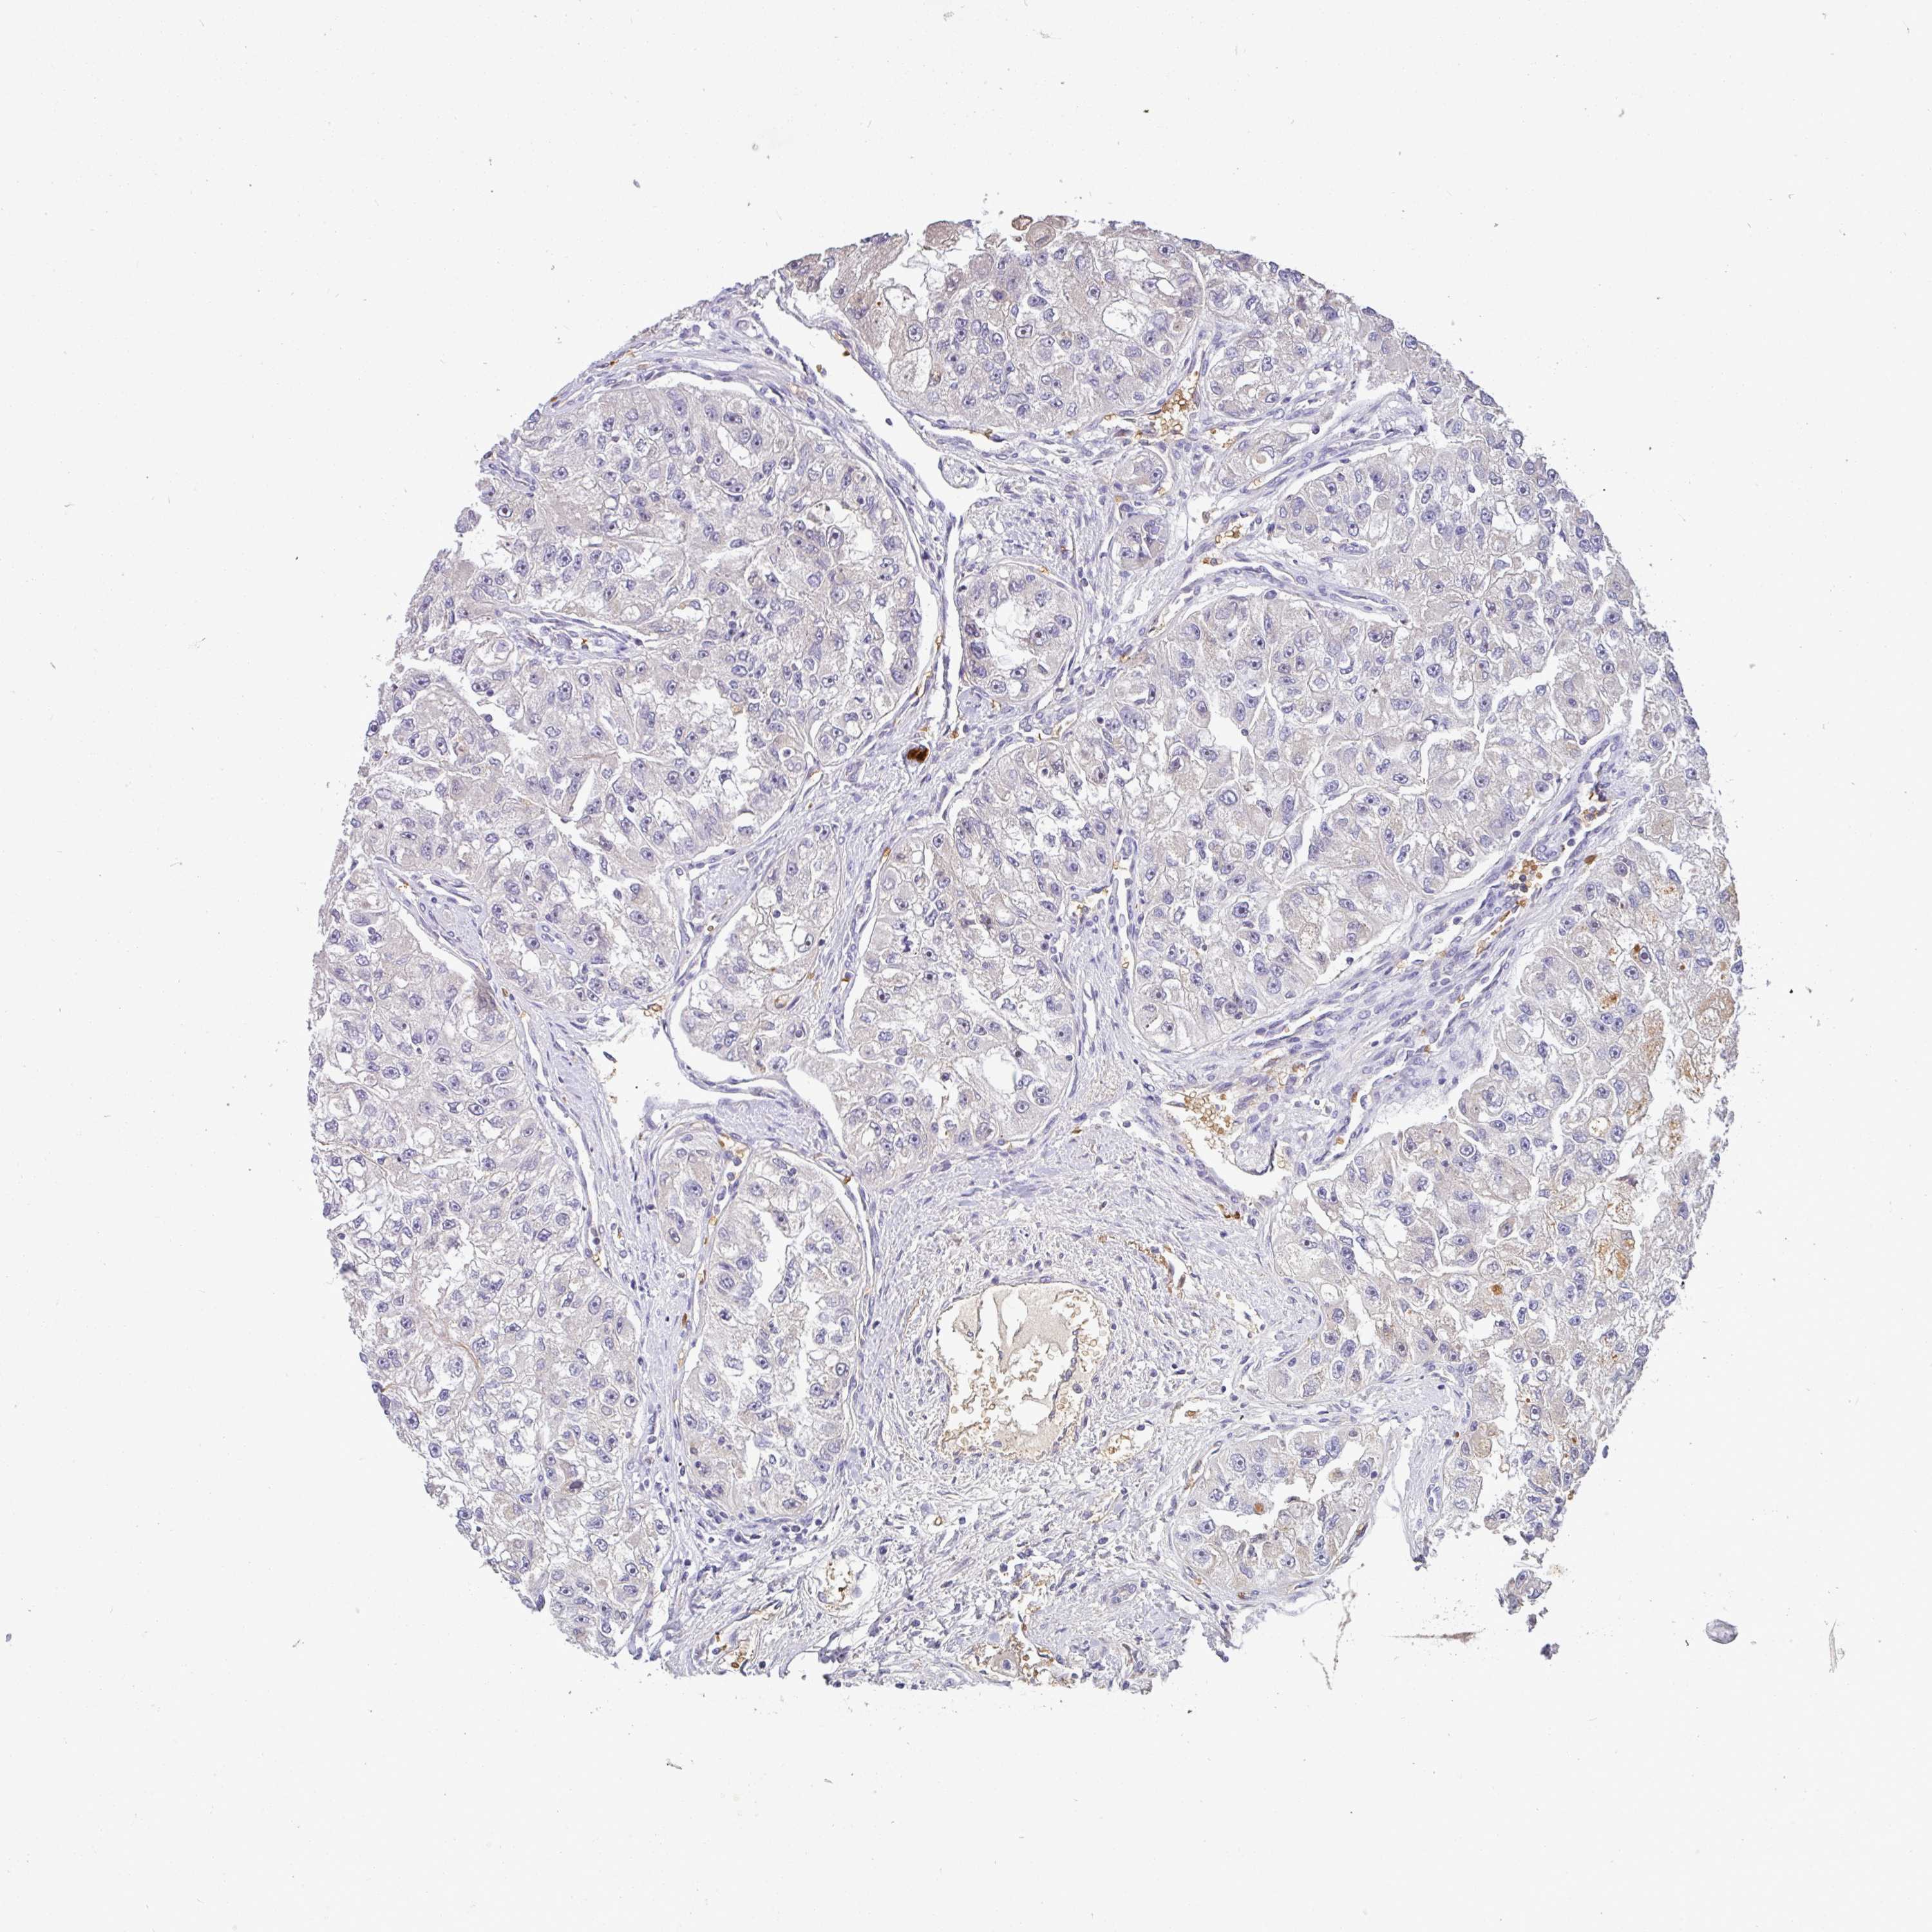

KIDNEY RENAL CLEAR CELL CARCINOMA (VALIDATION) - Interactive survival scatter ploti

The Survival Scatter plot shows the clinical status (i.e. dead or alive) for all individuals in the patient cohort, based on the same data that underlies the corresponding Kaplan-Meier plots. Patients that are alive at last time for follow-up are shown in blue and patients who have died during the study are shown in red.

The x-axis shows the expression levels (FPKM) of the investigated gene in the tumor tissue at the time of diagnosis. The y-axis shows the follow-up time after diagnosis (years). Both axes are complimented with kernel density curves demonstrating the data density over the axes. The top density plot shows the expression levels (FPKM) distribution among dead (red) and alive patients (blue). The right density plot shows the data density of the survived years of dead patients with high and low expression levels respectively, stratified using the cutoff indicated by the vertical dashed line through the Survival Scatter plot. This cutoff is automatically defined based on the FPKM cutoff that minimizes the p-score. The cutoff can be changed by dragging the vertical line or by entering a cutoff value in the square labeled "Current cut-off".

Under the Survival Scatter plot the p-score landscape (black curve; left axis) is shown together with dead median separation (red curve; right axis). Dead median separation is the difference in median mRNA expression between patients who have died with high and low expression, respectively. It is calculated as follows: median FPKM expression of dead patients with high expression - median FPKM expression of dead patients with low expression. This is intended to aid the user in visually exploring custom cutoffs and the associated p-scores and dead median separation.

Individual patient data is displayed and can be filtered by clicking on one or more of the category buttons on the top of the page. Categories describing expression level and patient information include: high, low, alive, dead, female, male and tumor stages. The scale of the x-axis can be toggled between linear and log-scale by clicking on the "x log" button. Mouse-over function shows TCGA ID, patient information and mRNA expression (FPKM) for each patient.

& Survival analysisi

Kaplan-Meier plots summarize results from analysis of correlation between mRNA expression level and patient survival. Patients were divided based on level of expression into one of the two groups "low" (under cut off) or "high" (over cut off). X-axis shows time for survival (years) and y-axis shows the probability of survival, where 1.0 corresponds to 100 percent.

C1QTNF9B is not prognostic in Kidney Renal Clear Cell Carcinoma (validation)

: 0.63

Average pTPM 1.3

Number of samples 100